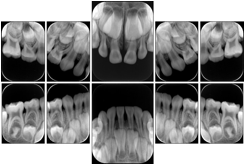

Intra-oral radiography typically involves acquisition of multiple images of various parts of the dentition. Many digital radiographic systems offer customized templates that are used for displaying the images in a study on the screen. These templates may also be referred to as mounts or view sets. The Structured Display Object represents a standard method of encoding and exchanging the layout and intended display of Structured Displays. A structured display object created in this manner could be stored with a study and exchanged with images to allow for complete reproduction of the original exam.

In most standard cases, images are oriented in structured layouts. These structured displays are useful to be shared between providers for reference purposes.

Table OO.1.1-1 shows structured display standard templates, where Viewset ID is based on the Japanese Society for Oral and Maxillofacial Radiology (JSOMR) classification provided by JIRA (Japan Medical Imaging and Radiological Systems Industries Association, www.jira-net.or.jp). Expected or typical teeth to be imaged location, region and designation codes are based on ISO 3950-2010, Dentistry - Designation system for teeth and areas of the oral cavity. For all the hanging protocols listed in OO.1.1-1, the value to use for Hanging Protocol Creator (0072,0008) is "JSOMR" and the value to use for Hanging Protocol Name (0072,0002) does not include "JSOMR" (e.g., "DL-S001A", not "JSOMR DL-S001A").